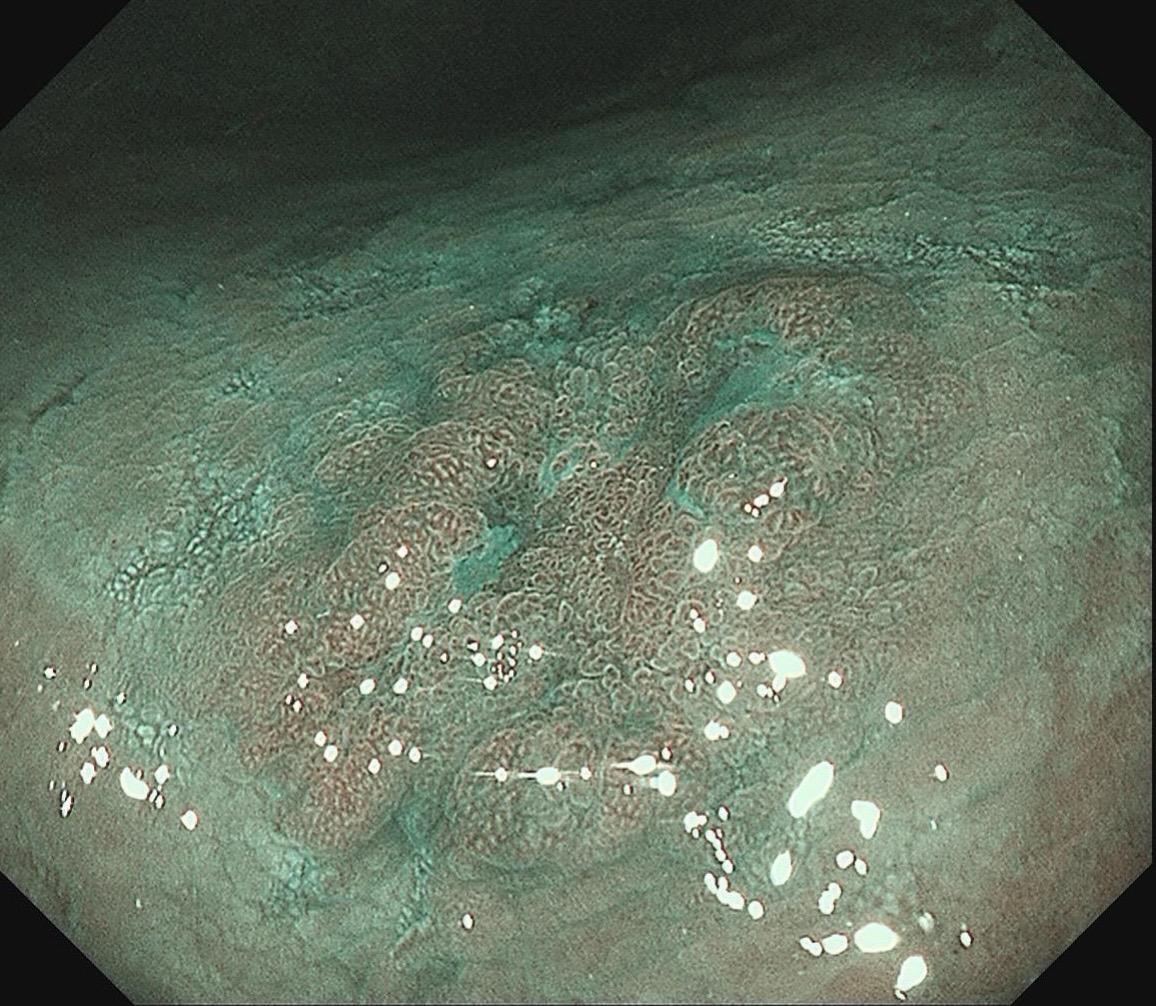

女,57岁,胃角。同事熟人,萎缩背景,色调淡黄,中央浅凹陷,腺管小而密集。